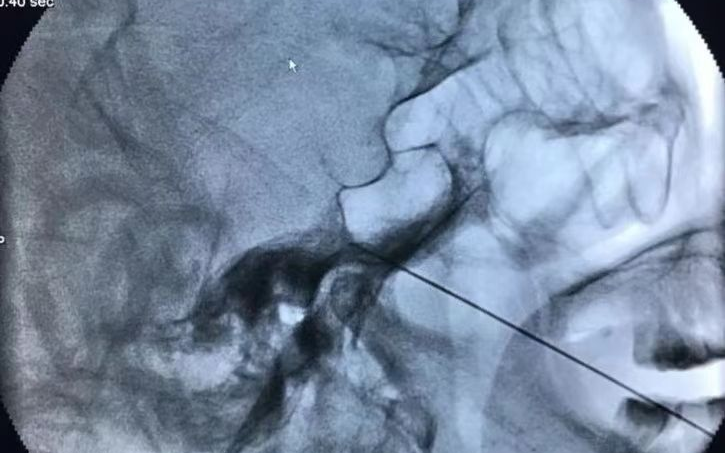

射頻神經(jīng)毀損術(shù)干預(yù)三叉神經(jīng)痛,是在X射線和CT引導(dǎo)下將射頻針經(jīng)皮刺入三叉神經(jīng)節(jié)處,選擇性破壞傳導(dǎo)痛覺、溫覺神經(jīng),達(dá)到止疼效果,適用于年老體衰有系統(tǒng)疾病,不能耐受手術(shù)者。

? 定位準(zhǔn)確:在C型臂或CT下精準(zhǔn)定位,射頻針直接作用在病變神經(jīng)上,數(shù)據(jù)精確到1毫米以下,角度誤差小于1度,且僅對病變神經(jīng)進(jìn)行處理。